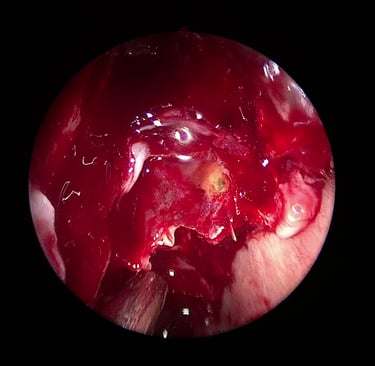

U odabranim slučajevima koristi se i intratekalni fluorescein, koji se ubrizgava u likvorski prostor – istjecanje se tada vidi pod plavim svjetlom, što olakšava pronalaženje mjesta defekta tijekom operacije

Danas je zlatni standard za većinu slučajeva likvoreje upravo endoskopska kirurgija nosa i baze lubanje. Ova tehnika omogućuje:

Precizno zatvaranje defekta kroz nosnice

Korištenje vlastitih tkiva (npr. septalna sluznica, masno tkivo, fascija) ili bioloških materijala za zatvaranje